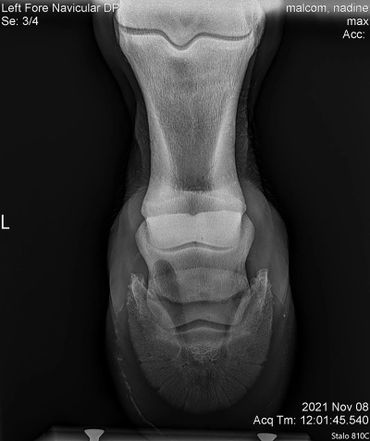

Due to an old injury Max was never sound on his front left. However, with Equioxx we have been able to keep him comfortable. He started going more lame on that foot so we had Dr. Johnson take a look at it. We did a nerve block and some x-rays to see what is going on. There are no significant changes to see so in the future on bad days we will just give him some banamine as well.